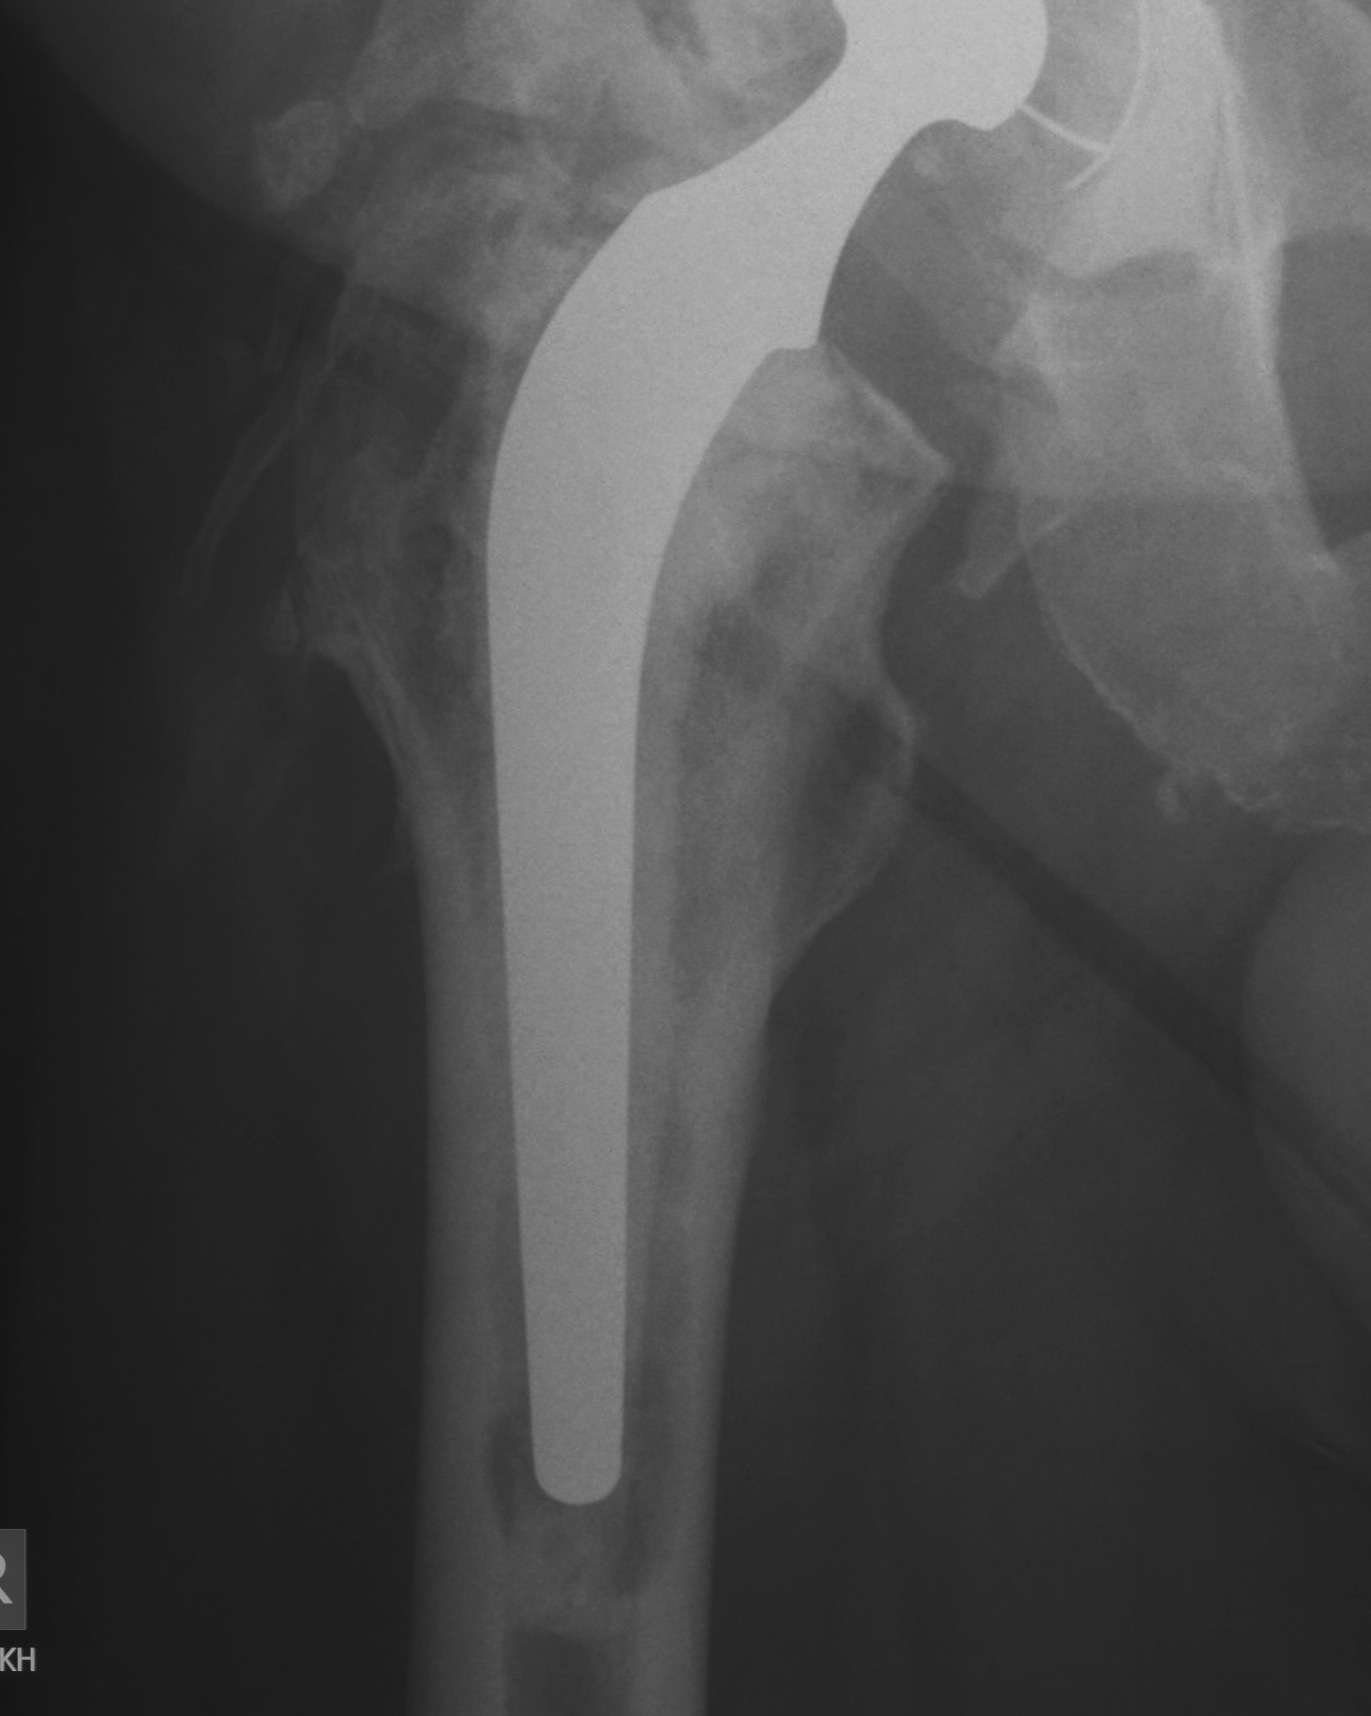

1. Long stem cemented revision femoral stem

Modern cementing techniques

Indications

- Paprosky Types I – IV

- very versatile

Technique

- complete removal / debridement of neocortex

- modern cementing techniques

Howie JBJS Br 2007

- 219 patients, 9 year follow up

- collarless double taper

- 98% 10 year survival

Problems

- ? increased non union with ETO